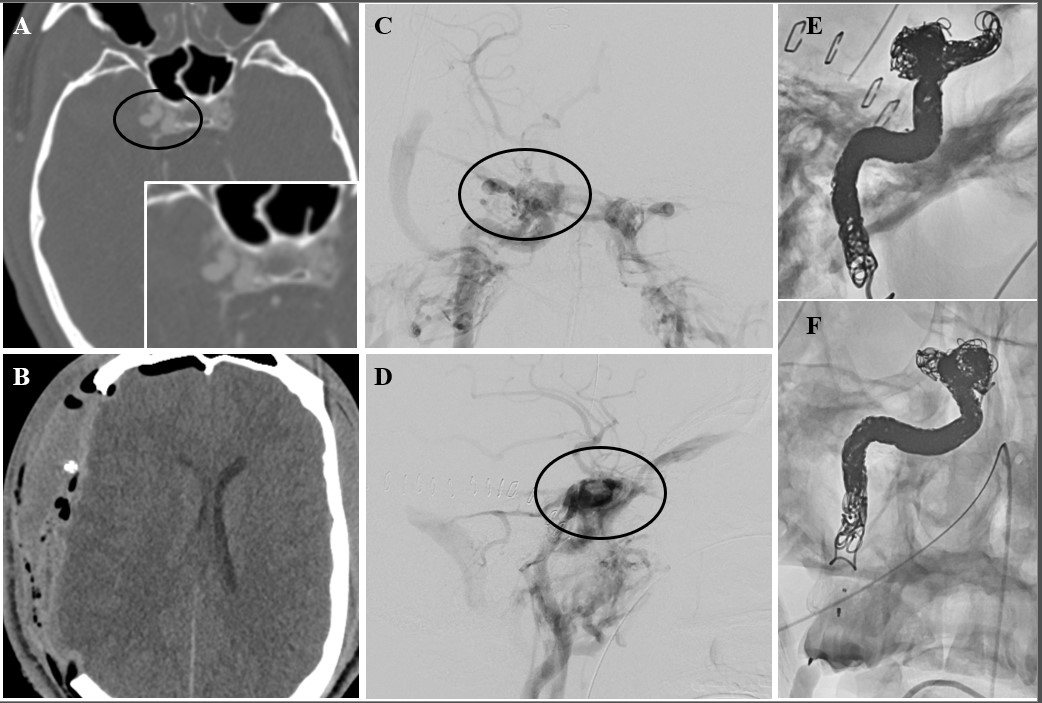

Choosing Vessel Imaging Modality before Surgical Intervention

In a recent study, Serra et al. suggested that a significant number of patients, up to 20% of those suffering a civilian GSWH, can develop a pseudoaneurysm in the hyper-acute window [14]. This number, despite being significantly higher than previous estimates, does not include other types of vascular injuries [6,9,11,25-27]. Importantly, while this study showed a CTA sensitivity in line with Meyer’s prospective study, it also demonstrated that patients presenting with a TICA had higher chances of developing an intracerebral hematoma [14]. Further, these subjects underwent surgery more often and suffered higher rates of bleed expansion and intraventricular hemorrhage. Another important factor to consider when evaluating new lesions discovered on CTA and not confirmed on DSA is the spontaneous obliteration of pseudoaneurysms, dissections, fistulas. This was again demonstrated by Serra et al. in their series, as nine patients (9/28, ~30%) underwent spontaneous TICA resolution on repeat CTA/DSA. Admission CTA might therefore cast light on the early phases after pTBI, where biological processes might explain part of the difference with DSA. In the future, further characterization with ultra-early DSA might be warranted in these subjects. This will allow to confirm the presence of TICAs and other vascular injuries seen on CTA, address these lesions early via endovascular technique, and provide important data to validate the use of CT in pTBI settings. A clinical trial of ultra-early CTA/DSA may significantly improve our understanding of GSWH pathophysiology, a problem that has become highly relevant in recent years, following the increase in civilian GSWs. CTA, despite the recent advancements in its sensitivity, is still outperformed by DSA in terms of pure sensitivity and specificity. Given its availability it can nonetheless play a pivotal role in the preoperative evaluation of pTBI – TICAs and PCVIs can be quickly identified, and the surgical approach modified to address these lesions. If noticed on admission CTA, TICAs can be trapped and excised or cauterized, reducing blood loss and the risk of subarachnoid hemorrhage (Figures 3 and 4). On the other hand, early DSA allows for direct obliteration of the lesion via Onyx, coils, glue [25,28,29]. While the advantages of treatment during angiography are frequently highlighted and used to justify early DSA, it is evident that in emergent scenarios where immediate decompression and debridement need to be performed, this exam can significantly delay care and affect patient prognosis. Further, open treatment of TICAs and PCVI has been routinely performed for decades, and it should be stressed that CTA streamlines surgical interventions by allowing the treatment of the lesion and cerebral decompression during the same session.

Post-operative DSA shows several truncated distal MCA branches and mass effect from packing. Follow-up DSA on day 10 post-injury failed to demonstrate additional vascular injuries.